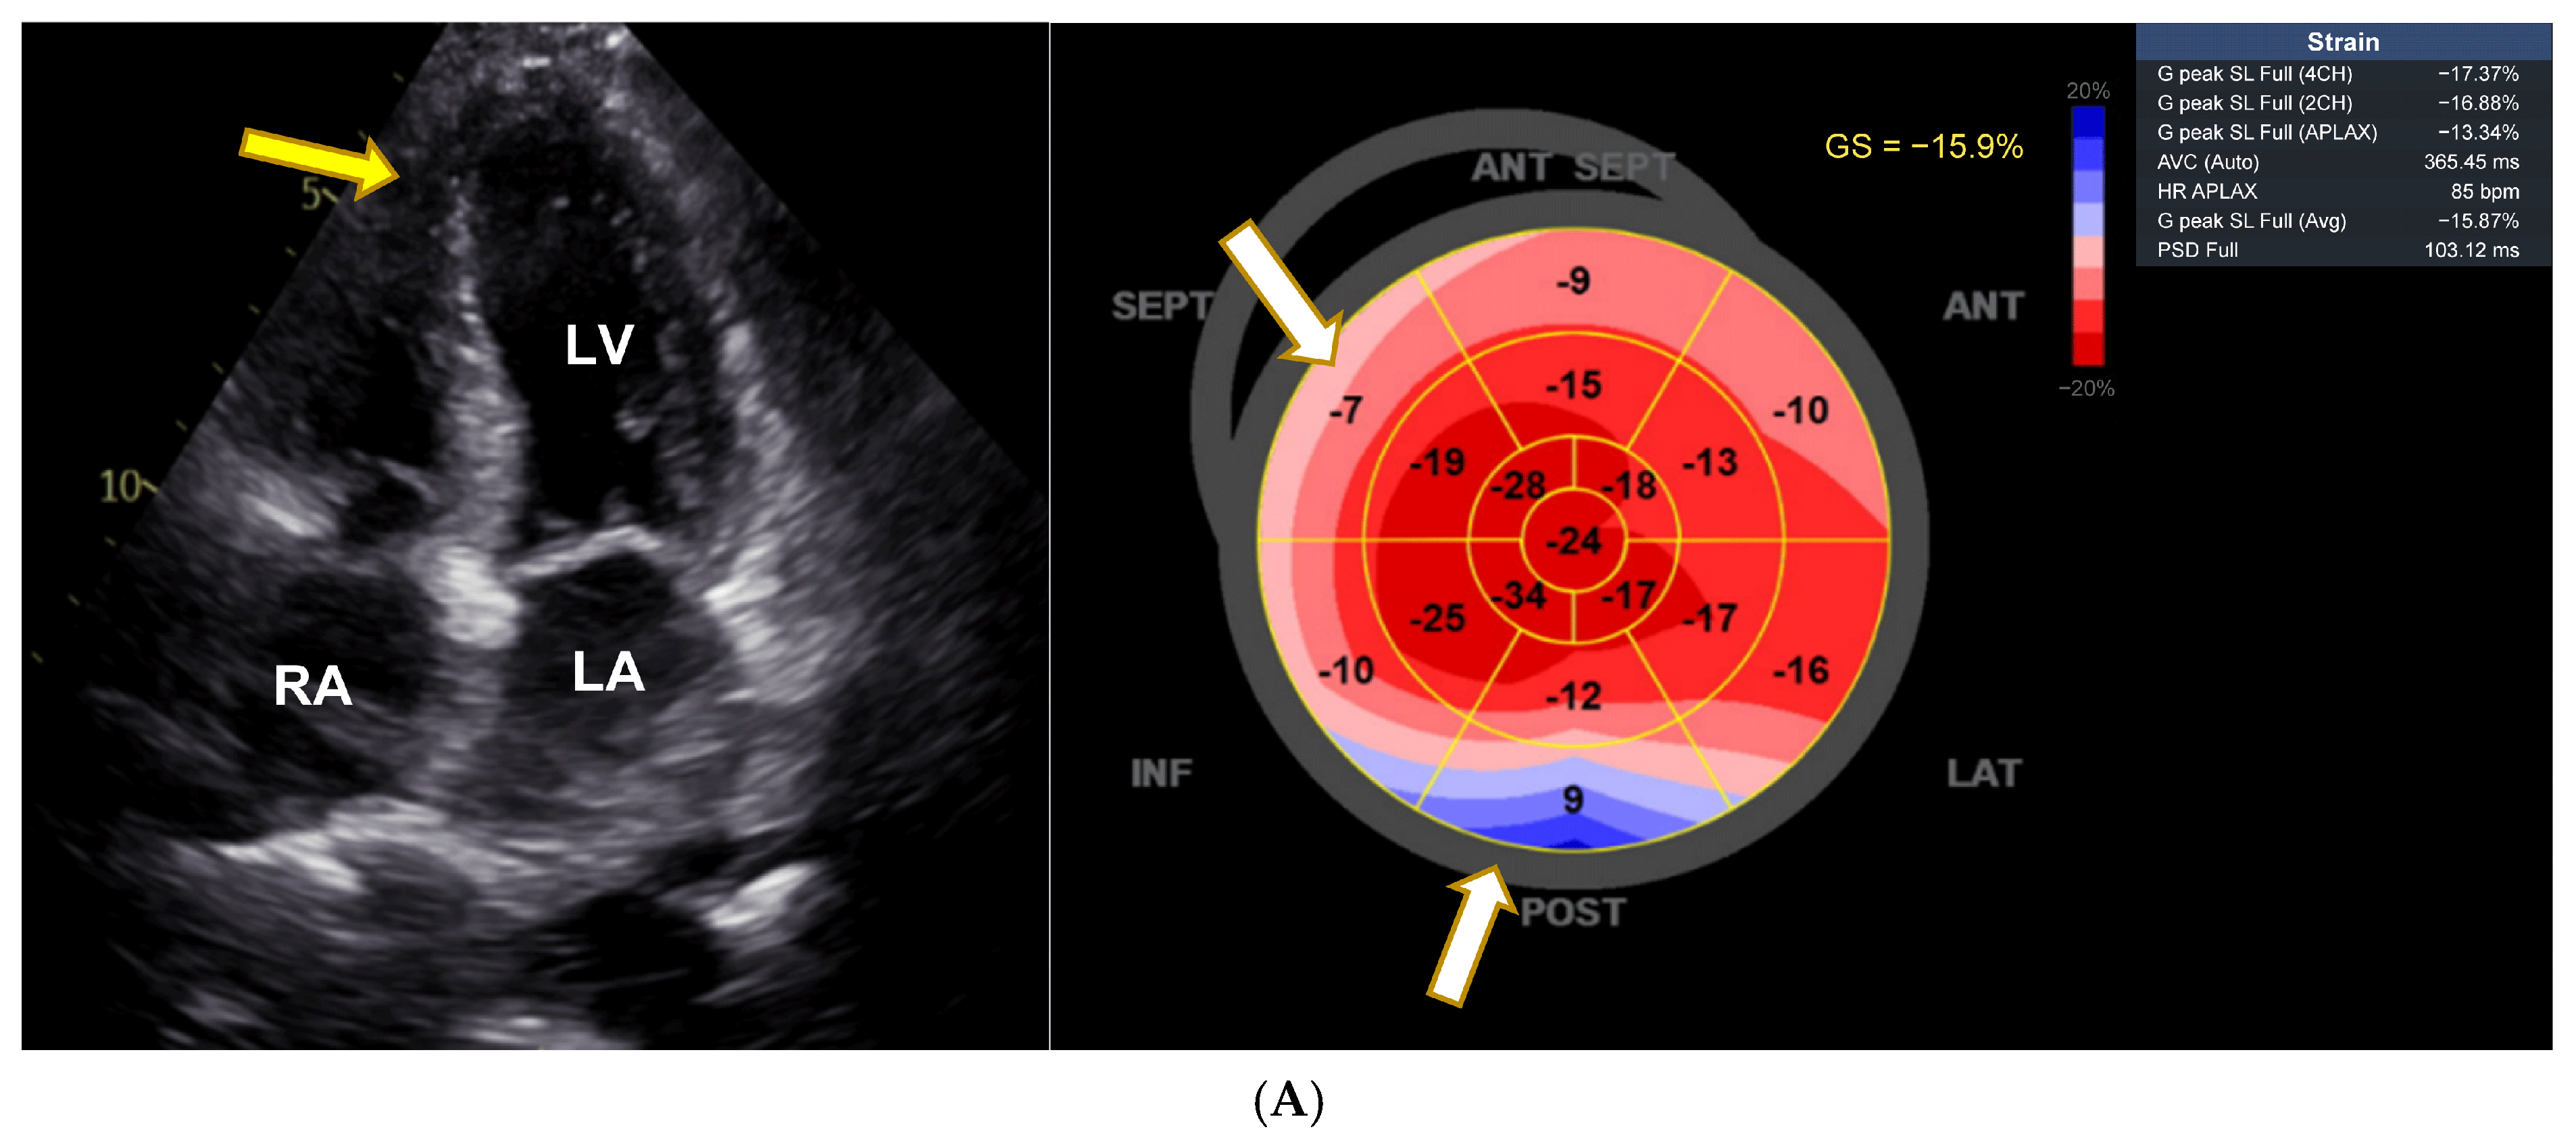

An 82-year-old man had been taking VEN for more than 8 years in a dose of up to 187.5 mg/day. LVEF had been documented as normal in the past. In spring 2023, he presented with severe heart failure, pleural effusions, edema, renal failure, massive increase in NT-proBNP (22,743 ng/L, age-adjusted normal < 450 ng/L), a dilated LV with severely diminished LVEF of 20% and impaired LV GLS (Figure 3A). Coronary angiography ruled out significant coronary artery disease. Other medications included bisoprolol, sacubitril/valsartan, torasemide, empagliflozin, tamsulosin, insulin, immunoglobulin treatment (i.v., every 2 weeks), and warfarin. The patient was also diabetic and had a history of necrotizing myositis, possibly due to statin treatment (thus the immune treatment), along with a history of sensory polyneuropathy, diabetes, and chronic issues related to previous subarachnoid hemorrhage. VEN was subsequently reduced to 75 mg/day. At the last follow-up in November 2024, he was asymptomatic; the biplane LVEF was 56% (normal 52–72%), and LV strain was borderline with a GLS of −16.7% (Figure 3B). NT-proBNP was normal at 227 ng/L. VEN serum concentrations were within normal limits (VEN 0.36 µmol/L, O-Desmethyl-VEN 0.18 µmol/L, VEN + O-Desmethyl-VEN 0.53 µmol/L; normal range 0.36–1.44 µmol/L). There was also stage 3b renal impairment, with an estimated glomerular filtration rate (eGFR) of 37 mL/min/m2.

Figure 3.

Severe impairment of LV ejection fraction parallel to reduction in LV strain, reversible after dose reduction. (A) During high-dose venlafaxine 187.5 mg therapy there is left ventricular (LV) hypertrophy (yellow arrows), a significantly reduced left ventricular ejection fraction (LVEF) of 20%, and severely impaired left ventricular global longitudinal strain (GLS) of −5.7%, indicating marked systolic dysfunction. LV = left ventricle, LA = left atrium. (B) Under venlafaxine 75 mg, a regression of left ventricular (LV) hypertrophy (yellow arrow) was observed, with an improvement in LV ejection fraction (LVEF) to 49% and an increase in left ventricular global longitudinal strain (GLS) to −16.7%.